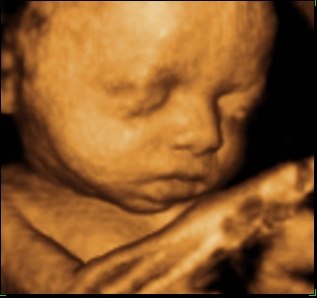

så var vi til 3D scanning i fredags. Så vild en oplevelse.. Hun er bare helt perfekt.

hun vejede 1423g, og så var hun en uge foran så det var da super dejligt at vide at lille pigen har det super og lever luxus derinde i maven

vi var heldige med at hun var rigtig aktiv plus vi også så hende med åbne øjne

Vedhæftede fotos (klik for at se i fuld størrelse)